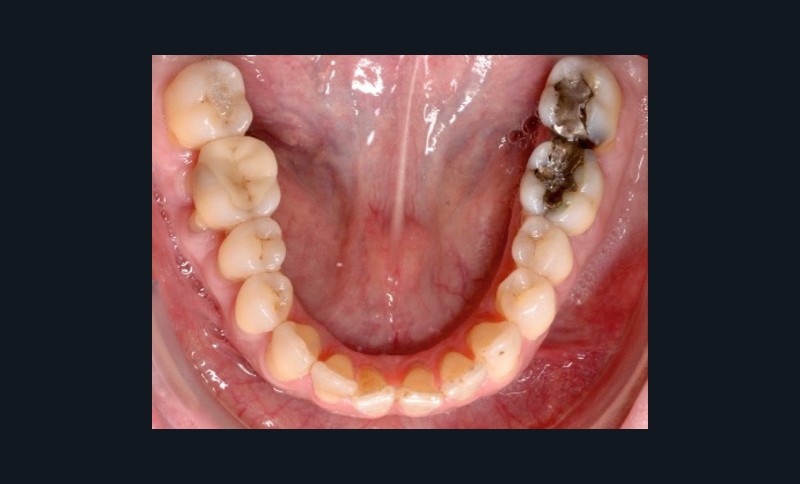

À l’examen endo-buccal (fig. 2), on note une formule dentaire complète (absence des 8) avec présence de restaurations multiples étanches, un bon contrôle de plaque et une parodontite de stade 4 grade C stabilisée [3], des récessions gingivales et des mobilités dentaires généralisées (degré 2, classification de Miller). L’arcade mandibulaire présente une courbe de spee importante avec égression du bloc incisivo-canin. Les milieux inter-incisifs sont alignés, le recouvrement est normal, le surplomb est augmenté à 3 mm et associé à des diastèmes et de la vestibulo-version des incisives maxillaires. Les relations antéro-postérieures canine et molaire sont en Classe I d’Angle.